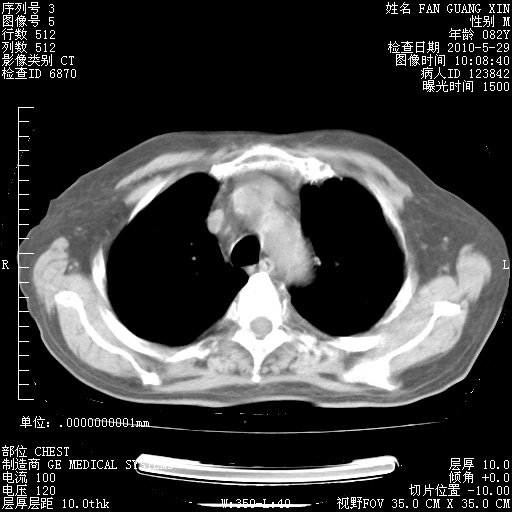

治疗3周后的肺部CT纵隔窗

再治疗10天后的肺部CT

再治疗10天后的肺部CT 纵膈窗

阅读此次胸部CT,肺间质渗出性改变较入院时有吸收。目前从体温、白细胞、中性分叶明显增高,肯定存在细菌感染(发生医院感染哦,若无消化道及泌尿系统等感染的依据,肺部感染可能大)。若你院头孢哌酮舒巴坦钠耐药率较高,同意你的方案,若48小时体温仍高,可考虑使用碳青霉稀类抗菌药物,同时可予超声雾化、注意滴数时加大液体量。白蛋白33.30g/L较低哦,需加强营养等支持治疗。